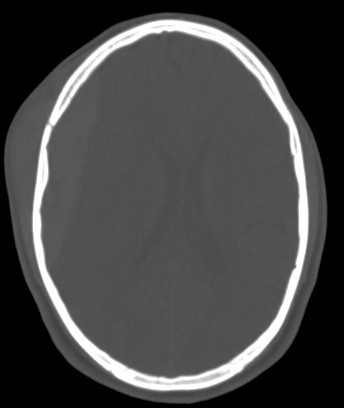

A brain CT scan, also known as a computed tomography scan or CAT scan, is a non-invasive imaging procedure that uses X-rays to create detailed cross-sectional images of the brain and surrounding structures. It's a common diagnostic tool for evaluating head injuries, strokes, brain tumors, and other neurological conditions. Here's a more detailed explanation: What it is: A brain CT scan uses a series of X-ray beams that rotate around the head, capturing multiple images from different angles. These images are then processed by a computer to create detailed cross-sectional views of the brain, allowing doctors to visualize the brain's structures and identify any abnormalities. The scan can be performed with or without contrast dye, which helps to highlight certain tissues and blood vessels for better visualization. Why it's used: Traumatic brain injuries: CT scans are often the first imaging test used to assess the extent of head injuries and identify potential fractures, bleeding, or swelling. Stroke: CT scans can quickly identify whether a stroke is caused by a blood clot (ischemic stroke) or bleeding (hemorrhagic stroke), guiding appropriate treatment. Brain tumors: CT scans can help detect and assess the size and location of brain tumors. Other neurological conditions: CT scans can also be used to diagnose conditions like hydrocephalus (excess fluid in the brain), aneurysms (bulges in blood vessels), and certain types of dementia. Guiding procedures: CT scans can be used to guide biopsies or other procedures involving the brain. What to expect during the procedure: You will lie on a table that slides into the CT scanner, which is a large, doughnut-shaped machine. The scan itself is painless, but some people may experience slight discomfort from lying still on the hard table. If contrast is used, you may feel a warm or flushing sensation, or a metallic taste in your mouth. The scan typically takes only a few minutes. Risks and Precautions: CT scans involve exposure to radiation, but the risk from a single scan is generally considered low. If you are pregnant, it's important to inform your doctor, as alternative imaging methods may be considered to avoid exposing the fetus to radiation. If you have any allergies, particularly to contrast dye, make sure to inform your doctor.